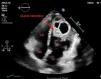

Presentamos el caso de un hombre de 33 años, procedente de Marruecos que consultó por disnea y molestias torácicas de 3 meses de evolución. En la ecografía (fig. 1) se identificó una masa quística en ápex del ventrículo izquierdo y se completó el diagnóstico con RNM, en la que se caracterizó un quiste hiperintenso en T2 (fig. 2). Los síntomas de la hidatidosis cardiaca dependen del grado de compresión pericárdico y coronarioy de la masa. La ecografía transtorácica ofrece una buena sensibilidad y especificidad para llegar al diagnóstico, que se confirmó mediante anatomía patológica durante la intervención, que consistió en resección de vesículas con protección del lecho quirúrgico con suero hipertónico escolicida. Al alta se mantuvo tratamiento con albendazol durante al menos 6 meses.